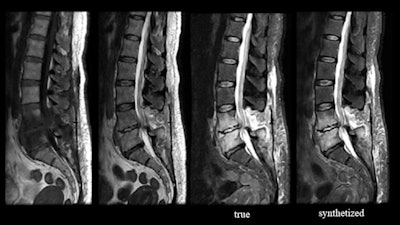

Looking ahead, efforts are currently underway to apply deep learning to produce synthetic image contrasts, using AI to reconstruct multiple contrasts from one scan, Tanenbaum said.

AI may also help to address concerns regarding the use of gadolinium-based contrast agents. For example, Subtle Medical is developing SubtleGAD, a work-in-progress application that applies deep learning to synthesize post-contrast enhanced images from lower contrast-enhanced images. The software can generate images with 90% less gadolinium dose that look very much like a full-dose image, according to Tanenbaum.